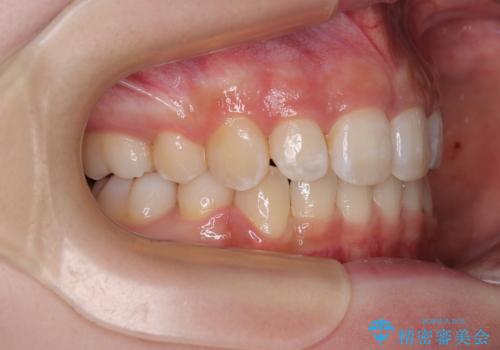

抜歯矯正により、下唇が前方に突出した感覚が大幅に改善されました。